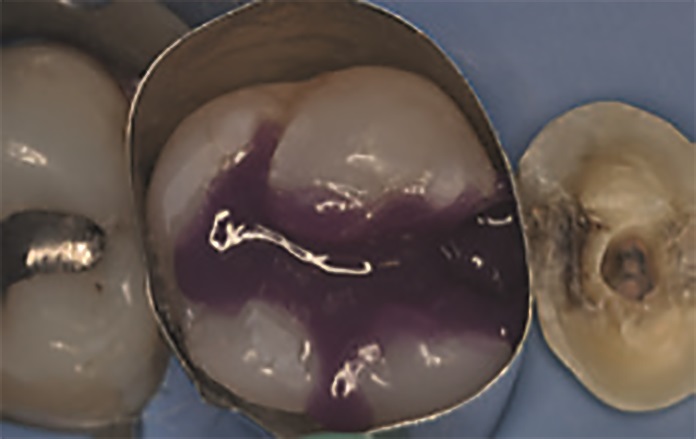

Na drugiej wizycie pacjentka poprosiła o estetyczną wymianę dwóch wypełnień amalgamatowych na zębach 16 i 14. Po doborze koloru wypełnienia uzyskano izolację pola zabiegowego za pomocą koferdamu OptiDam™ (Kerr). Wypełnienia amalgamatowe zostały usunięte pod obfitym strumieniem wody (ryc. 4). Procedura adhezyjna w zębie 16 została przeprowadzona za pomocą OptiBond Universal, z zastosowaniem protokołu wytrawiania total‑etch. Po nałożeniu formówki Adapt SuperCap Matrix (Kerr), opracowanej specjalnie do dużych uzupełnień w odcinku bocznym, na całą opracowaną wcześniej powierzchnię zęba nałożono żel zawierający 37,5% kwasu ortofosforowego (Gel Etchant, Kerr) (ryc. 5). Po 15 sekundach ubytek został dokładnie wypłukany, a następnie osuszony delikatnym strumieniem powietrza. Takie postępowanie zapobiega zapadnięciu się włókien kolagenowych, co skutkowałoby ograniczeniem infiltracji systemu łączącego.